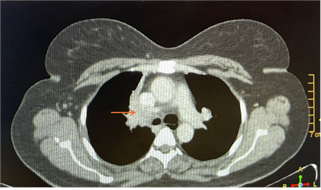

loss, or pain. Her medical history was unremarkable. A chest CT scan (Figure 1)

revealed an exo-endoluminal mass lesion occluding the right main stem bronchus;

Figure 1. CT thorax

showing right bronchial hypodense endoluminal mass (arrow).